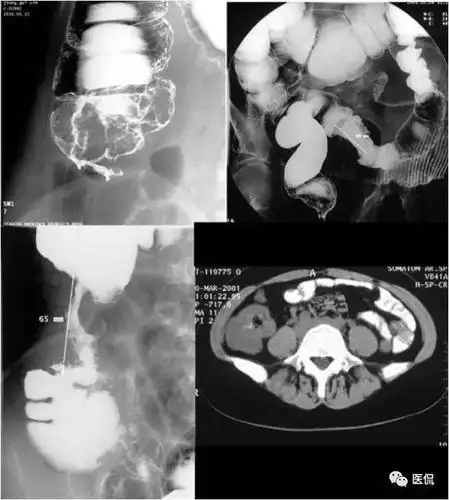

图3-41 胃溃疡型癌,钡餐检查,见腔外不规则龛影,有"环堤"及"指压迹"征

龛影位于胃轮廓之内,龛影外围绕以宽窄不等的透明带即 环堤,轮廓不

胃溃疡型癌,钡餐检查,见腔外不规则龛影,有"环堤"及"指压迹"征图3-42